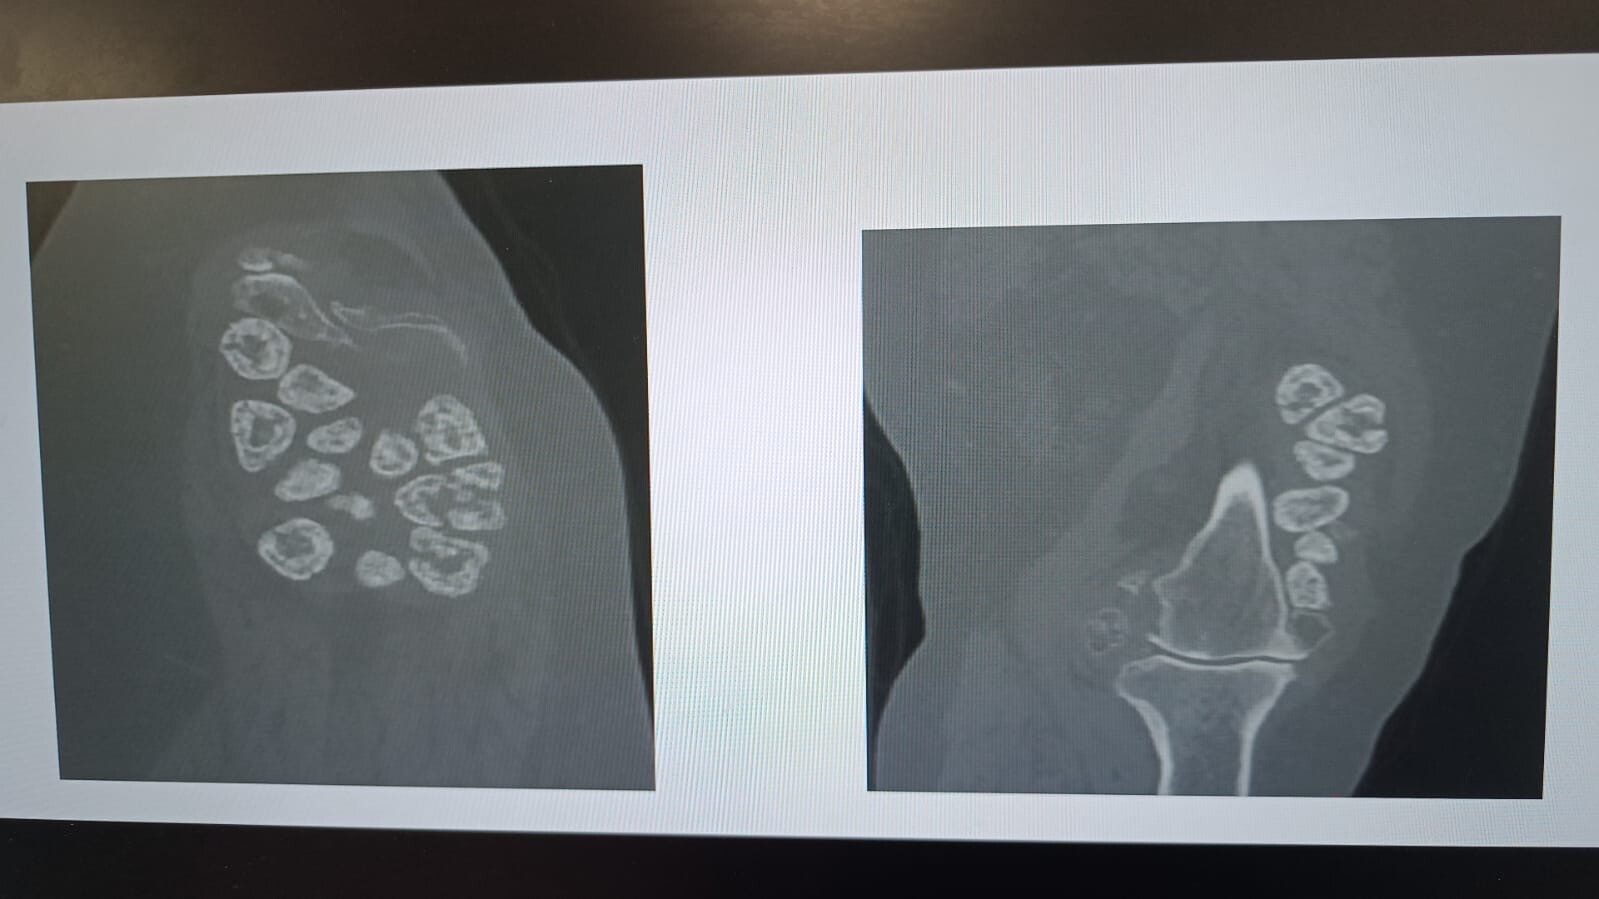

Malatya’da yaşayan 73 yaşındaki Elif Büyükbirer, 15 yıldır çektiği diz ağrısı ve hareket kısıtlılığı nedeniyle başvurduğu birçok merkezde sonuç alamayınca, son çare olarak İnönü Üniversitesi Turgut Özal Tıp Merkezi’ne geldi. Yapılan tetkiklerde Büyükbirer’in diz ekleminde hem kireçlenme hem de nadir görülen “sinovyal kondromatozis” hastalığına bağlı 24 adet taşlaşmış tümör tespit edildi.

Operasyonla ilgili bilgi veren Prof. Dr. Sevimli, “Elif Hanım’a dizinde hem tümör hem de kireçlenmeden dolayı ilginç bir ameliyat yaptık. İkisinin bir arada bulunması hem literatürde hem de meslek hayatımızda nadir görülen bir durum. Ekleminde ‘eklem taşları’ veya ‘eklem incileri’ dediğimiz ortalama 24 adet kitle vardı. Bunları çıkardıktan sonra total diz protezi ameliyatını gerçekleştirdik. Aynı anda hem tümörleri temizledik hem de kireçlenmeden dolayı ekleme protez taktık.” dedi.

Ameliyatın başarıyla tamamlandığını belirten Sevimli, “Bu tarz vakalar çok nadir görülür. Genellikle bir veya iki tümör çıkarırız ama bu hastamızda 24 adet taşlaşmış kitle tespit ettik. Bunlar iyi huylu kemik kitleleri olsa da ağrı ve hareket kısıtlılığına neden oluyordu. Şu anda hastamızın yürüyüşü serbest ve dizini rahatça katlayabiliyor. Kısa sürede taburcu edeceğiz.” ifadelerini kullandı.